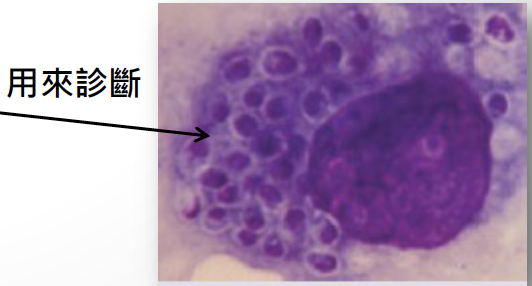

- 檢測

- Pap smear 子宮抹片

- 巴潘尼克氏染色法( Papanicolaou stain )

- koilocytotic (一圈透明)

- koilocytotic (一圈透明)